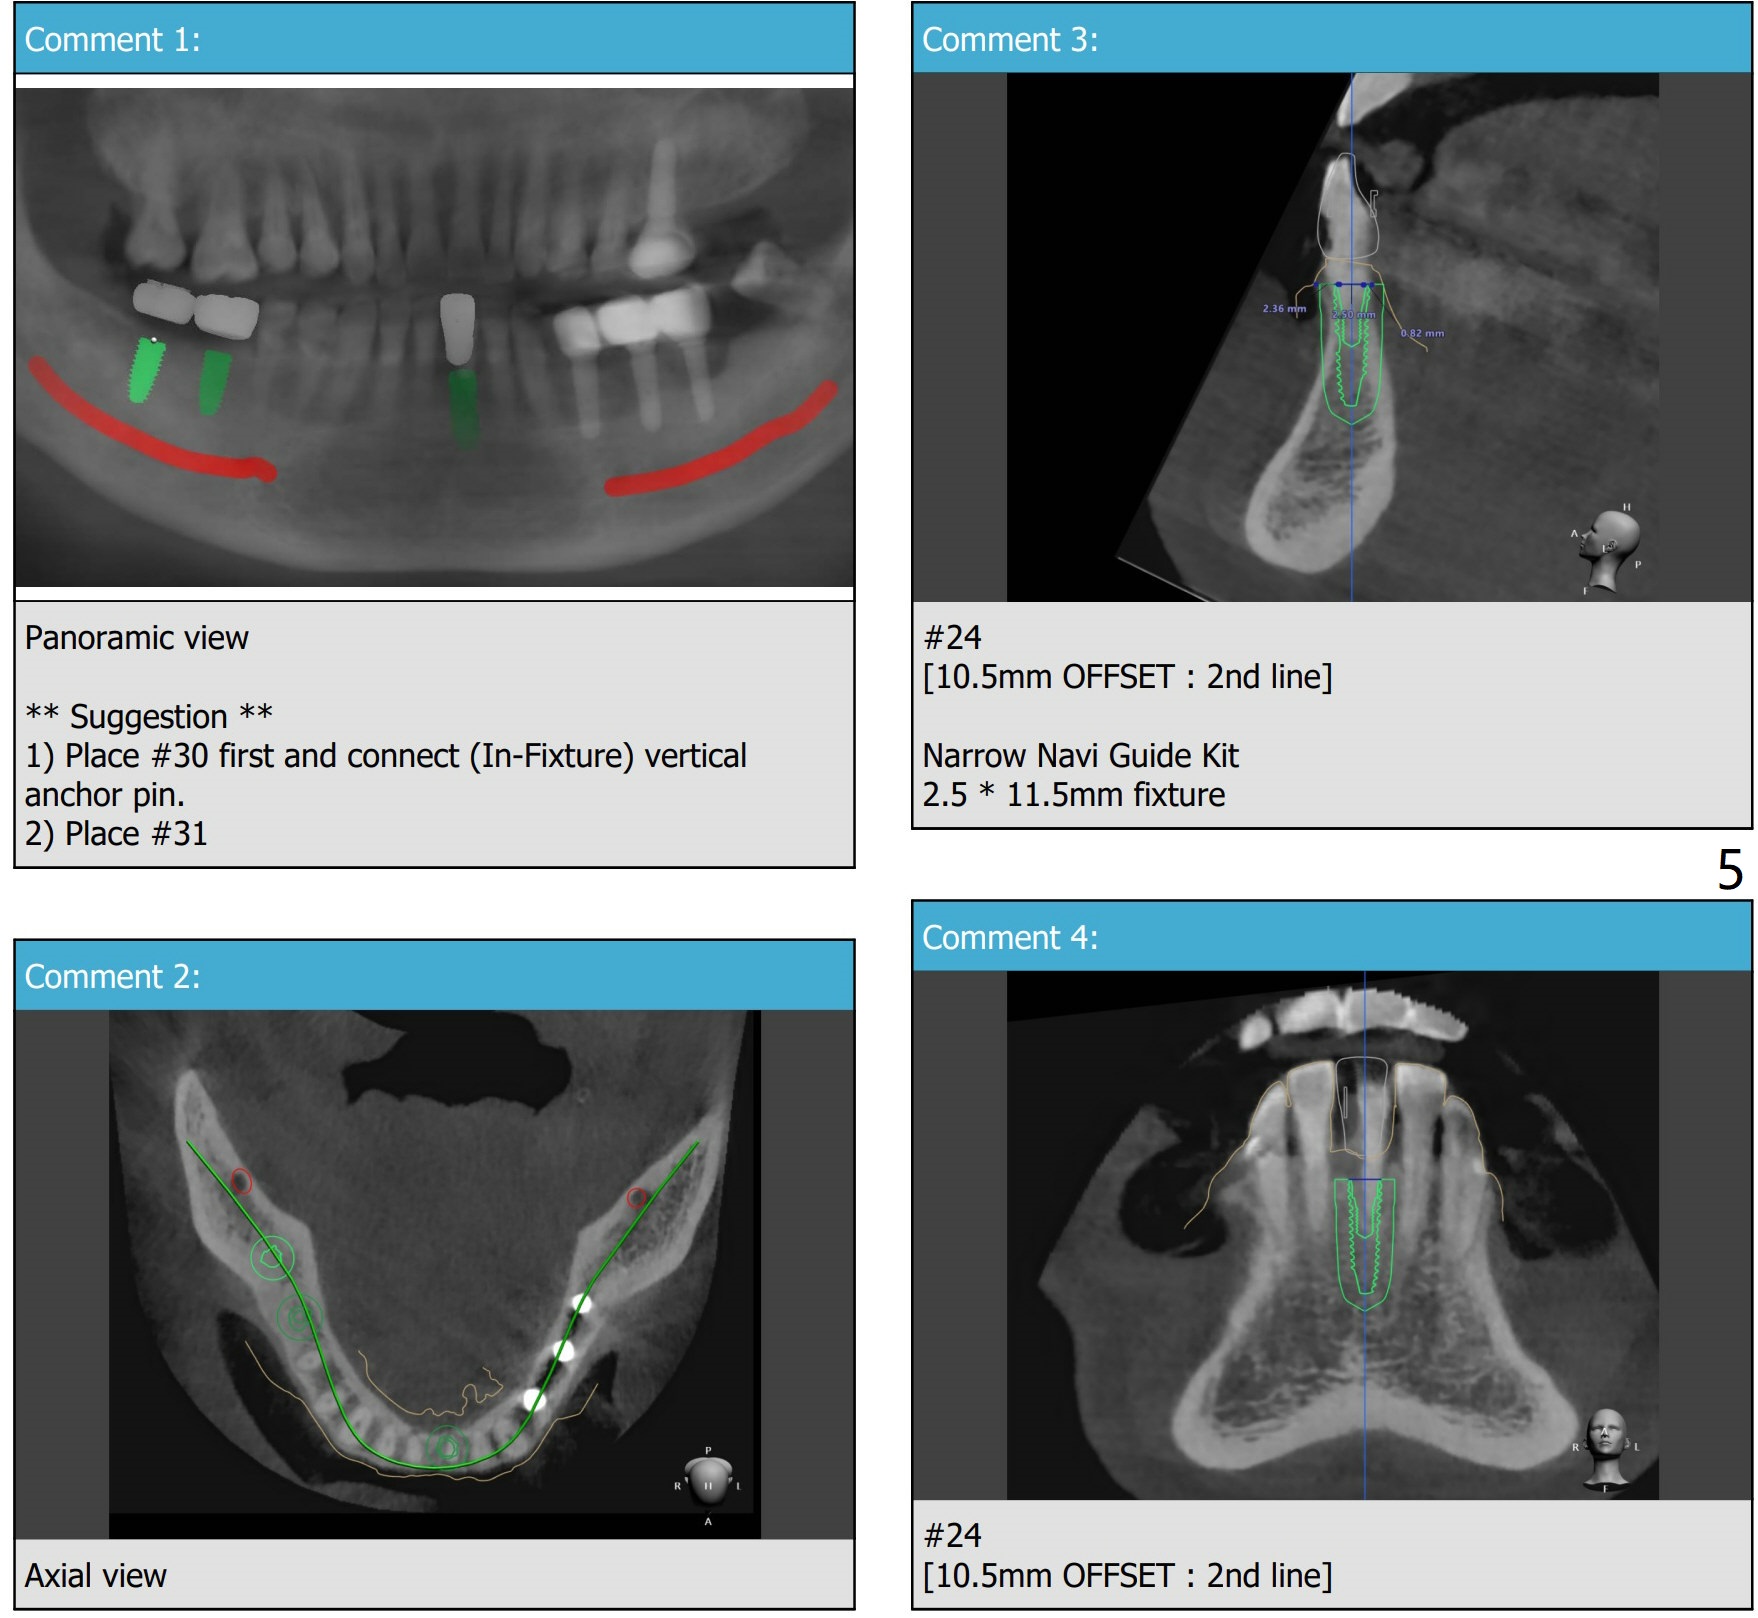

There is about 6mm of clearance between the supraerupted #2 and the implant platform (Fig.8). Barely enough. There is plenty of the apical bone at #30 (Fig.9). It is safe to place a 4.5x11 mm IBS implant. But the apical bone at #31 is not a lot. It is better to place 4.5x9 or 10 (UF?) mm implant at #31. If the bone density is not high at #24 (Fig.10), do not use the last drill fully.